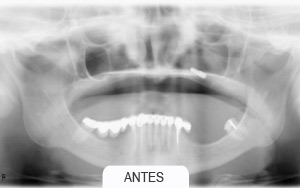

Casos Clínicos

Implantes dentales. Rehabilitaciones complejas